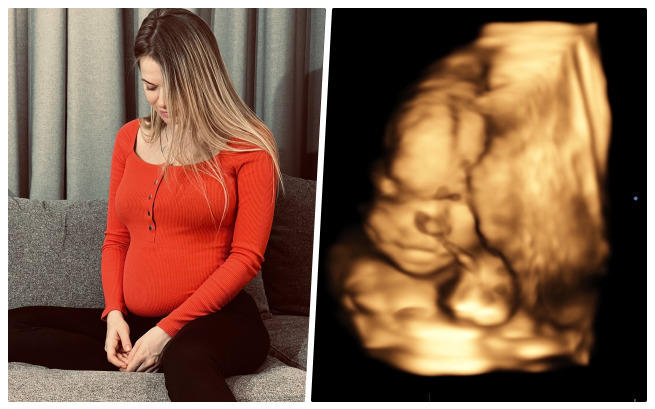

Śmierć dziecka - dobrze wiemy, czym jest. Straciliśmy dwoje, zanim zdążyliśmy je wziąć na ręce i przytulić... Gdy po latach starań zobaczyliśmy dwie kreski na teście ciążowym, byliśmy najszczęśliwszymi ludźmi na świecie. Do czasu... Nasza córeczka jest śmiertelnie chora. Bez pilnej operacji umrze... Mamy czas do lutego, by uratować jej życie. W ciągu tygodnia musimy zapłacić klinice 50 tysięcy euro! Błagamy o ratunek!

Euforia, że już niedługo wezmę na ręce swoje maleństwo, zawróciła mi w głowie. Dbałam o siebie ze wszystkich sił... Regularnie robiłam wszystkie potrzebne badania, odwiedzałam lekarzy, dużo spacerowałam i wyobrażałam sobie moment, w którym pierwszy raz przytulę moją kruszynkę. Nie potrafię opisać, co czułam, gdy po raz pierwszy w życiu usłyszałam na USG serce dziecka... Gdy usłyszałam „Gratuluję, będziesz mieć zdrową dziewczynkę ”. Codziennie rozmawiałam z moją córeczką... Mówiłam jej, jaki kolor będzie mieć jej pokój, jak będziemy spędzać wakacje u babci, że będziemy mieć psa...

Szłam na kolejne badanie USG... Pamiętam, że mój mąż ubierał choinkę, że czekały pod nią nowe zabawki, które kupiliśmy maleństwu... Wychodziłam z uśmiechem na ustach, wyobrażając sobie, że kolejne Święta spędzimy już we trójkę. Wracałam zrozpaczona, ze złamanym sercem... USG. Gabinet. Długa cisza... A potem słowa lekarza. Powiedział, że nie może zrozumieć, dlaczego nie widzi prawej strony przepony i że widzi jakiś dziwny cień w miejscu prawego płuca... Dostałam skierowanie na szczegółowe badania. Mąż towarzyszył mi tym razem, podczas badania USG oboje płakaliśmy i nie mogliśmy przestać...

Nasza córeczka ma jedną z najcięższych wad, rozpoznawanych w ciąży - prawostronną przepuklinę przeponową... To bardzo rzadka wada, która powoduje, że narządy znajdujące się w jamie brzusznej przesuwają się do klatki piersiowej, powodując zakłócenia w pracy płuc i serca... Wasilisę uratuje tylko operacja. Jeśli nie pomożemy jej teraz, po narodzinach czeka ją śmierć!

Na początku lutego muszę znaleźć się w szpitalu. Najpóźniej pod koniec miesiąca, kiedy będę w 28. tygodniu ciąży, lekarze muszą przeprowadzić operację... Wprowadzą specjalny balon, dzięki któremu płuca rosną i wypychają z klatki piersiowej nadmiar narządów, co po urodzeniu pozwoli na pracę płuc dziecka. Nasza córeczka może żyć!

Sami nigdy nie uzbieramy tych pieniędzy... Jesteśmy zwykłym małżeństwem, które tylko chce, by ich upragnione dziecko żyło. Jestem w 22. tygodniu ciąży, operacja musi się odbyć maksymalnie za 6 tygodni. Wiemy, że naszej dziewczynce można pomóc i nigdy sobie nie wybaczymy, że tego nie zrobiliśmy.